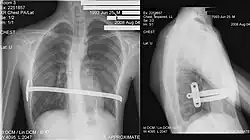

Pectus excavatum on PA chest radiograph with shift of heart shadow to the left and radioopacity of the right paracardiac lung field

Chest x-rays are also useful in the diagnosis. The chest x-ray in pectus excavatum can show an opacity in the right lung area that can be mistaken for an infiltrate (such as that seen with pneumonia).[23] Some studies also suggest that the Haller index can be calculated based on chest x-ray as opposed to CT scanning in individuals who have no limitation in their function.[24]